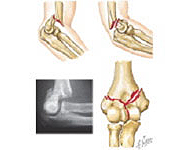

Luxaciones del codo

La articulación del codo tiene lugar entre el húmero y el cúbito y radio. La luxación de codo tiene lugar con mayor frecuencia en la segunda década de la vida. La separación traumática entre brazo y antebrazo es frecuente en el ámbito deportivo, especialmente en aquellos deportes que pueden provocar impactos sobre la mano con el codo en extensión. Ello es posible en artes marciales, futbol, baloncesto y escalada, entre otros.

Esta lesión no sólo compromete las estructuras óseas sino las ligamentosas y neurovasculares por lo que se requiere un meticuloso estudio en el servicio de urgencias para diagnosticar el grado de afectación tratándolo entonces adecuadamente.

En un primer momento la recolocación del codo en situación anatómica es primordial a través de un suave gesto y en algunas ocasiones bajo anestesia. Si a pesar de la congruencia articular, el codo se presenta inestable, puede ser necesario reforzar la estabilidad ósea con una intervención quirúrgica.